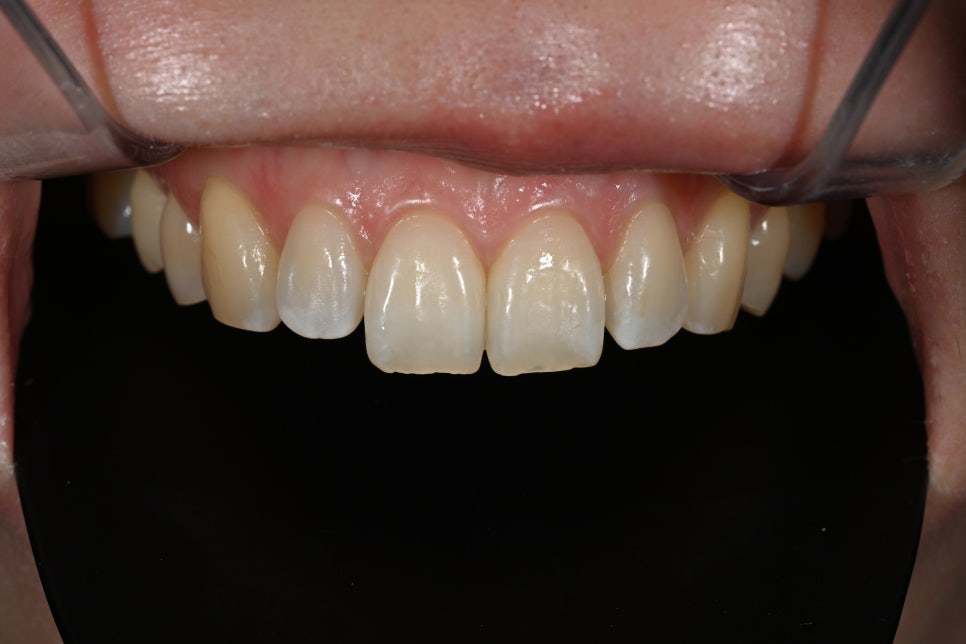

Changes after treatment

<BEFORE>

<AFTER>

After treatment, the patient experienced

a natural smile

a softer change in impression

greater satisfaction in photos

In particular, there were many comments like

"I can't tell that they had laminates"

"It just feels like they became prettier."

This is exactly the result of

Obzero Pure Laminates.